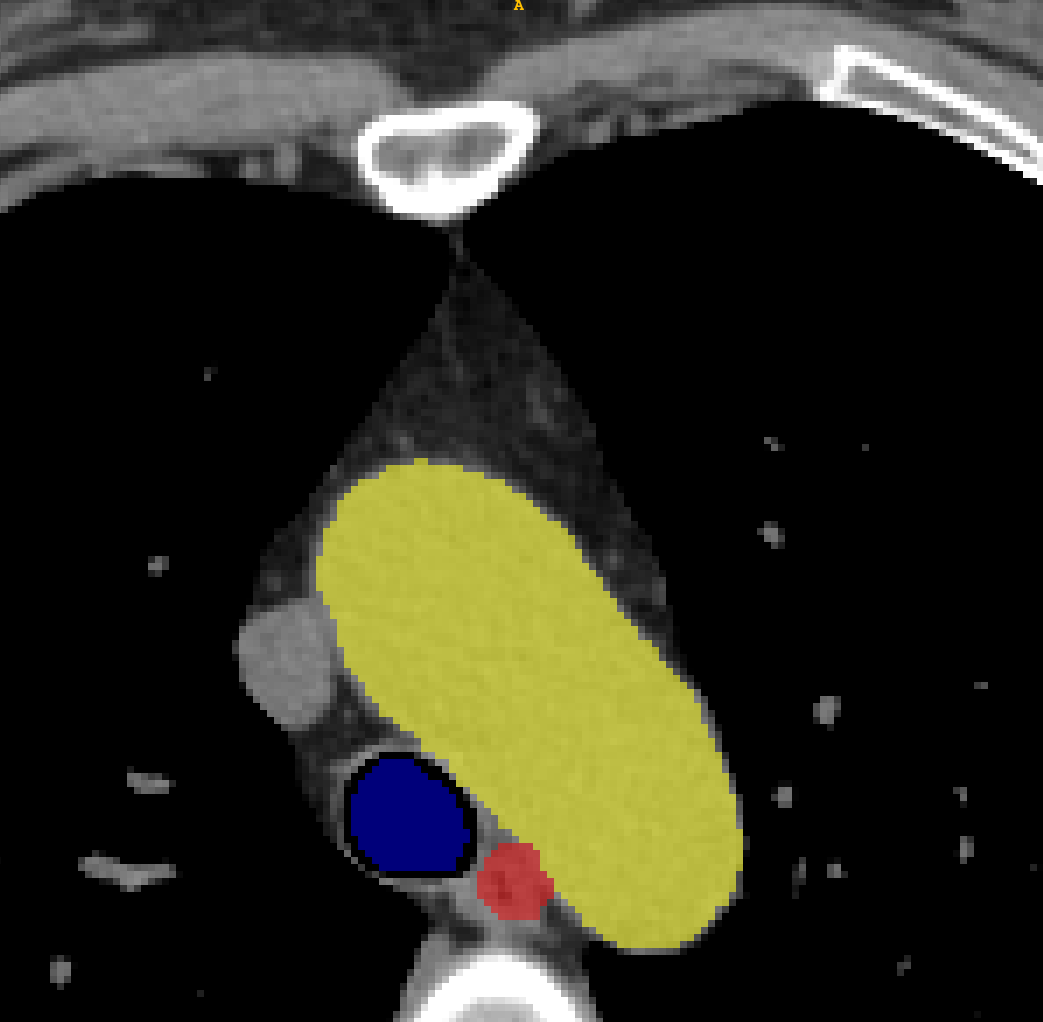

TABLE V: Visualization result on SegTHOR. Gray image registration result(row 1-2) shows the fitting ability of various methods. Mask image registration result(row 3-4) shows the regional continuity of various methods. The mask includes four parts: heart(green), aorta(yellow), trachea(blue) and esophagus(red).

[Uncaptioned image] [Uncaptioned image] [Uncaptioned image] [Uncaptioned image] [Uncaptioned image] [Uncaptioned image]

F M VoxelMorph Ants deedsBCV Ours

We selected four images of large deformations occurring at different locations from different CT, the visualization results are shown in Table V.

Rows 1-2 shows the CT gray image registration results. The task is to register MM to FF. From the visualization of gray image results, we can see that although ANTs and deedsBCV has high dice scores, the visualization results look unrealistic. Meanwhile, deep learning methods look smoother. The sixth column shows the results of our method. The fitting effect is improved compared to previous methods.

Rows 3-4 shows the mask registration results. The background of each image is FF. We could judge the performance by observing the fitting degree of the mask and background. In many practical tasks, we use a registration algorithm to register MM’mask to get the mask of FF. There may be a situation where the gray image fitting is good, but the mask result is poor. This may be because the continuity of the registration field is not good enough.